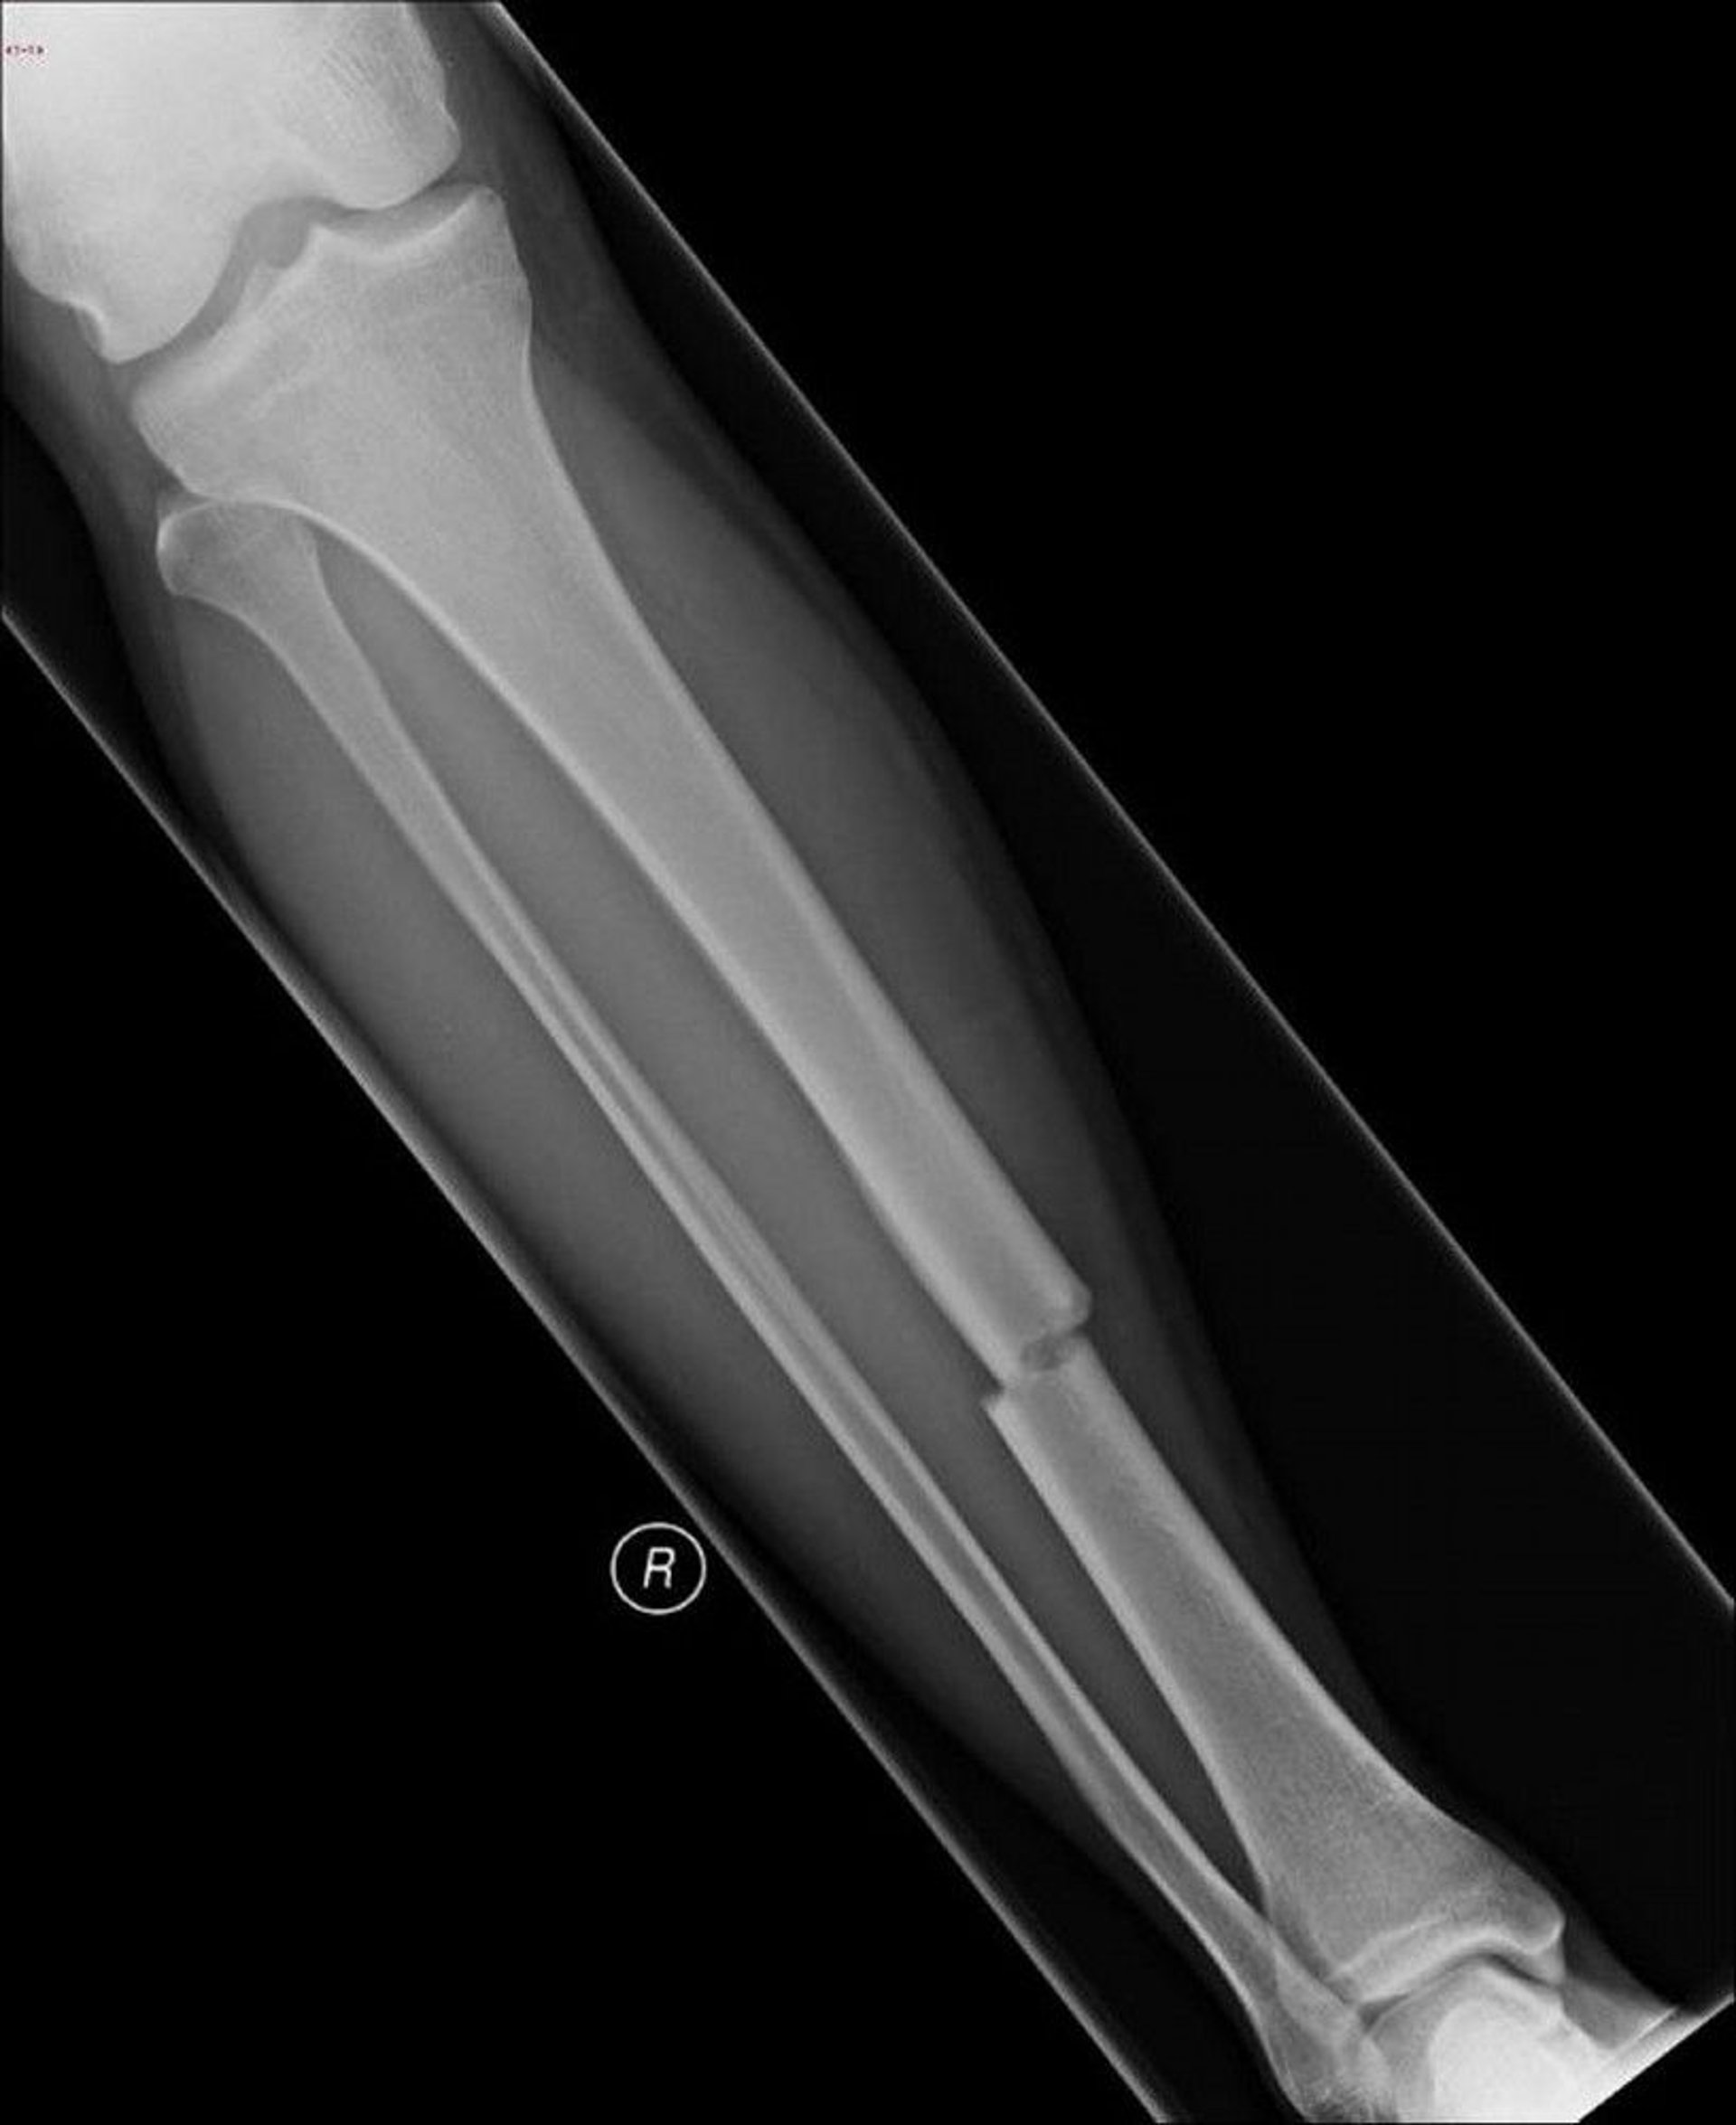

Fraktur adalah retak atau patah pada tulang. Sebagian besar fraktur terjadi akibat kekuatan yang diberikan pada tulang.

• Dokter terkadang dapat mendiagnosis fraktur berdasarkan gejala, keadaan yang menyebabkan cedera, dan hasil pemeriksaan fisik, tetapi pemeriksaan sinar-x biasanya perlu dilakukan.

• Pemeriksaan sinar-x untuk mengidentifikasi fraktur

Pemeriksaan Sinar-X adalah tes yang paling penting dan biasanya merupakan tes pertama dan satu-satunya yang dilakukan untuk mendiagnosis fraktur.

Pemeriksaan sinar-x biasanya diambil dari setidaknya dua sudut untuk memperlihatkan kesejajaran fragmen tulang. Sinar-x rutin ini mungkin tidak menunjukkan fraktur kecil ketika potongan-potongan tulang yang patah tetap berada pada tempatnya (yaitu, tidak terpisah menjadi fragmen). Fraktur tersebut disebut fraktur okult (tersembunyi). Jadi terkadang pemeriksaan sinar-x tambahan diambil dari sudut yang berbeda. Kadang-kadang, dokter menunggu untuk melakukan pemeriksaan sinar-x selama beberapa hari atau bahkan beberapa minggu karena beberapa fraktur bersifat samar, seperti fraktur tulang rusuk, fraktur stres, dan fraktur pergelangan tangan skapoid, baru terlihat pada pemeriksaan sinar-x setelah fraktur mulai sembuh dan kalsium disimpan di tulang yang baru.

Tes pencitraan memungkinkan dokter untuk mengidentifikasi jenis fraktur dan menggambarkannya dengan tepat.